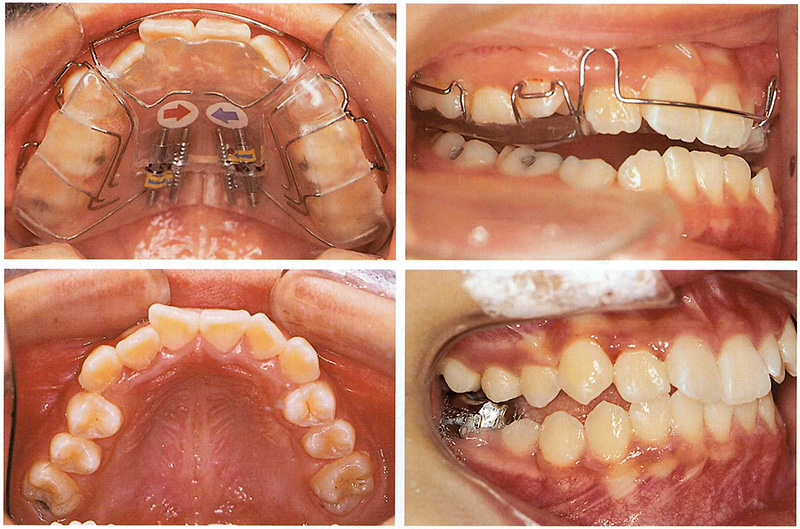

A patient had crowding in the upper canine area, a crossbite on one side, and a second premolar that was trapped and unable to erupt. Instead of waiting until adulthood (which might have required extraction-based orthodontics), we used a special removable appliance called a Sagittal Appliance to gently move the front teeth forward and molars backward, creating room for proper eruption.

This appliance includes push springs to move the incisors forward and distal screws to expand the space for the premolars—one of the most complex and precise devices to make!

In a similar textbook case, a patient who wore a sagittal appliance had dramatic results: both impacted canines erupted naturally, and the crossbite was corrected—avoiding the need for extraction orthodontics later.